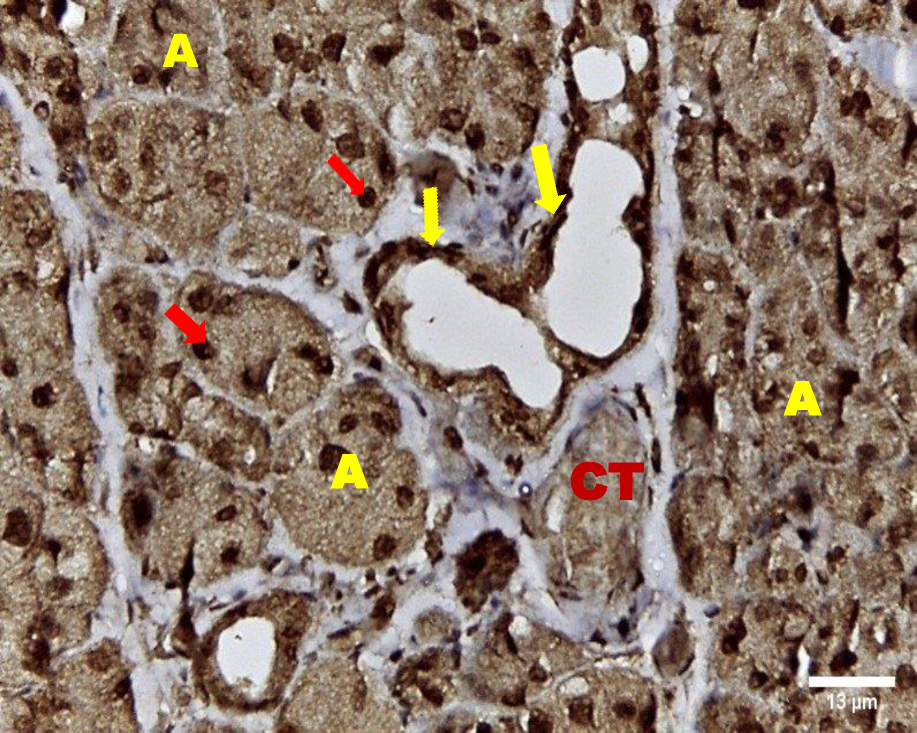

Immunohistochemical examination

Immunohistochemical investigation of parotid glands of group A on day 14 revealed strong cytoplasmic, membranous and nuclear expression of EGF in both acini and ducts. There was no staining in the connective tissue. Immunostained specimens from the same group on day 30 showed strong membranous, cytoplasmic and nuclear expression of the EGF in acinar & ductal cells. Few scattered serous cells showed no nuclear expression. The connective tissue showed no expression (Figure 6, Figure 7).

Immunohistochemical investigation of parotid glands of group B on day 14 showed weak membranous, moderate cytoplasmic and nuclear reactivity of acinar cells. Some acinar cells showed no nuclear expression. The ductal cells showed strong membranous, cytoplasmic and nuclear expression. There was no immunoreactivity in the connective tissue. Immunostained sections from the same group on day 30 showed weak membranous, cytoplasmic and negative nuclear expression in serous cells. The duct system revealed strong membranous, cytoplasmic and nuclear expression. The connective tissue did not stain for EGF (Figure 8, Figure 9).

Noticeably, the immunohistochemical results in the current study supported the histological results - strong cytoplasmic, membranous and nuclear EGF expression of acini and ducts in group A on day 14 and day 30 was observed. These results were in agreement with Shang et al. who demonstrated upregulation of EGF in most mucoepidermoid carcinomas, which surges to 80% in case of lymph node metastases.30

The results of this study demonstrated strong nuclear expression within the acini of group A at day 14 and day 30, which was clarified by Dittmann et al. who concluded that upon cell irradiation EGF-EGFR complex are translocated to the cell nucleus, principally in regions with uncoiled chromatin (euchromatin) because these areas are easily accessible for DNA repair processes after exposure to irradiation.31

Moreover, Vuorinen, Rajala, Ihalainen, and Kallioniemi found that the complex is linked to co-transport of some associated proteins such as Ku70 and Ku80 as well as protein phosphatase 1 which is linked to the nucleus and is involved in the regulation of DNA-protein kinase. Nuclear import of the EGFR-linked complex is permitted by a karyopherin-dependent process which plays an important role in the process of regeneration.32

Group B in the current study demonstrated weak membranous, moderate cytoplasmic and nuclear reactivity on day 14, while on day 30 it showed weak membranous, cytoplasmic and no nuclear expression of EGF. These results were explained by Dittmann et al. who reported that the use of radical scavengers eliminated radiation-induced EGF nuclear translocation.31 Moreover, the connective tissue of all groups showed no EGF expression, which is in agreement with Zhuang, and Liu who assumed that EGF and EGFR are located mainly in epithelial cells not in the connective tissue under normal or pathologic conditions.33